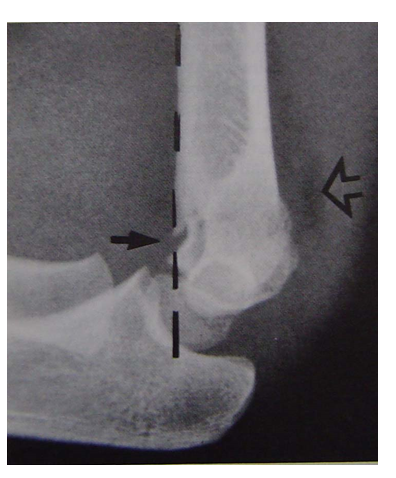

• 伸直型骨折复位后,肘关节屈曲,X线正位

• 很难判断内或外翻,侧位投照容易。

• X线正位投照方法

• 肘关节最大屈曲

• 片盒放在肘关节下

• 球管90度针对片盒